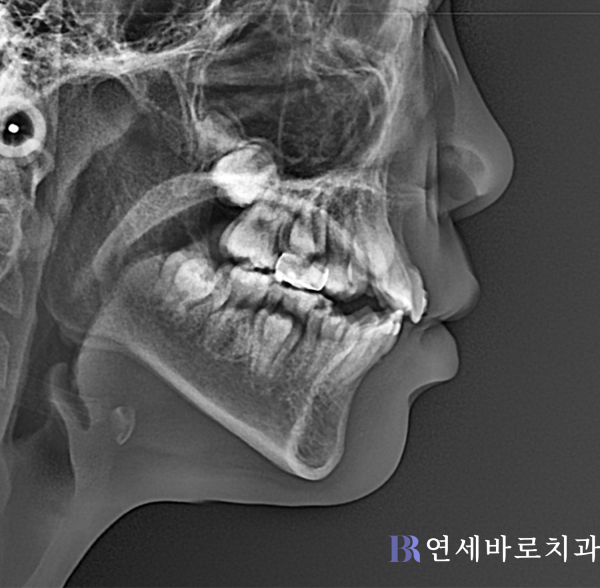

엑스레이 상으로 볼 때, 상악 왼쪽 송곳니가 나올 공간이 사라진 상태였습니다. 그러면서 전체적으로 치열이 비뚤어지기 시작한 것으로 보였는데요.

바로 인접한 측절치가 뒤로 움직인 모습이 관찰됐습니다. 그러면서 앞니 사이에 공간이 생겼네요. 이런 식의 치아 이동이 치열 전반에 영향을 끼쳤습니다.

상악 중절치까지 틈새가 넓어진 것이 확인되었습니다. 뿐만 아니라 아랫니도 배열이 틀어져 있었는데요. 때문에 중심선이 비뚤어진 점도 관찰됐습니다.